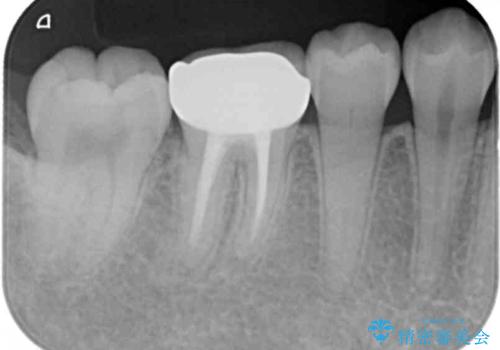

- 右下6 仮歯+ジルコニアクラウン 11,000円+110,000円費用は治療当時の料金となります

インレーにすると残った歯が薄くなってしまう場合は術後の破折リスクが高いためクラウンで修復することがあります。